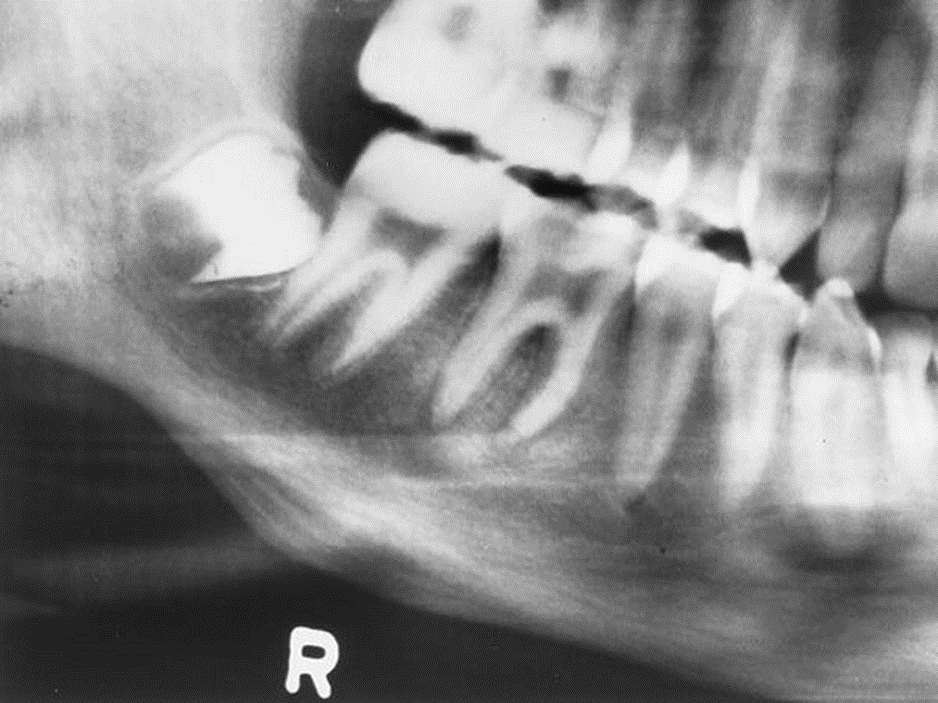

2. Bill is an asymptomatic 47-year-old who presented for routine dental treatment. This radiograph was taken as part of the full mouth survey.

What is your diagnosis?